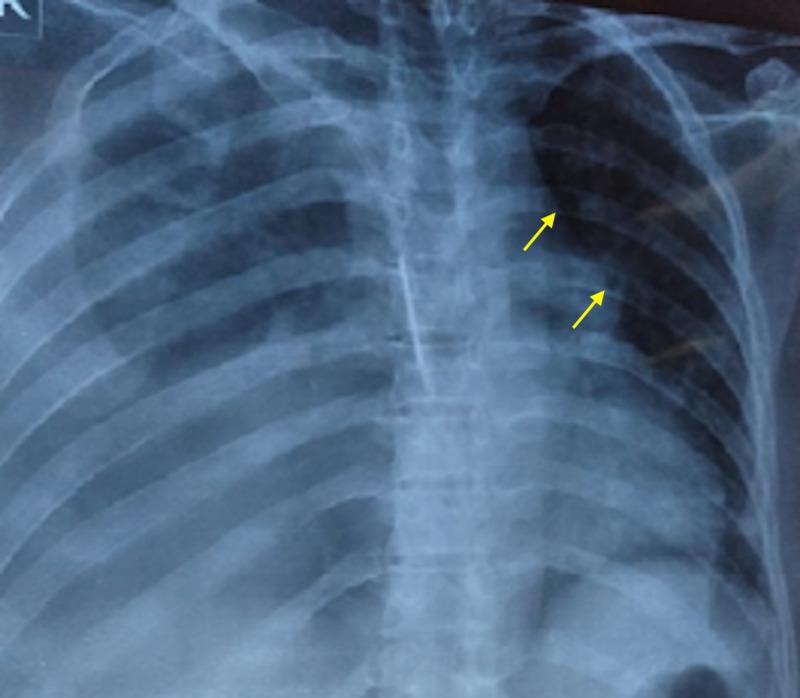

Multiple myeloma (MM), a common hematologic malignancy, is predominantly a disease of old age with a median age at diagnosis hovering around 70 years. Medical literature remains largely bereft of reports of the ailment in young female patients. We chronicle the case of a 26-year-old female patient who presented with a history of fever, weight loss, constipation, frequent infections, and back and chest pain. Laboratory workup divulged underlying anemia, renal impairment, increased calcium, and significant urinary proteins, insinuating a diagnosis of MM. Subsequent bone marrow examination confirmed a diagnosis of MM. Following treatment with a concoction of dexamethasone, cyclophosphamide and bortezomib, the patient improved rapidly, and her clinical symptoms abated. This article further accentuates the need for physicians to be cognizant of the possibility of early-onset MM in unusually young patients.

多发性骨髓瘤(MM)是一种常见的血液系统恶性肿瘤,主要是一种老年疾病,诊断时的中位年龄徘徊在70岁左右。医学文献中关于年轻女性患者患此病的报道仍然很少。我们记录了一名26岁女性患者的病例,她有发热、体重减轻、便秘、频繁感染以及背部和胸部疼痛的病史。实验室检查发现有潜在的贫血、肾功能损害、血钙升高和大量尿蛋白,提示诊断为MM。随后的骨髓检查确诊为MM。在用地塞米松、环磷酰胺和硼替佐米联合治疗后,患者迅速好转,临床症状减轻。本文进一步强调了医生需要认识到异常年轻患者中早发性MM的可能性。